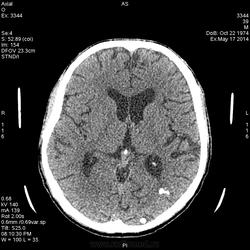

Здравствуйе Уважаемые коллеги! Представляю снимки головы, пациент поступил в приемное с судорожным припадком. Вот что увидел:

Пока написал менингиомы? Будем делать с контрастированием. Я совсем не маэстро в онкологии, поэтому вызывают сомнения данные образования. Жду Ваших мнений.

Тоже не большой знаток: 1. АВМ, 2. паразит. Для менингиом не характерное расположение.

Вот расположение и не подходит для менингиом, поэтому хочу контраст сделать, может прояснит ситуацию

А, что контраст даст при таких обызвествлениях? Возможно посмотреть сосуды и связь с кальцинатами.

Туберозный склероз исключайте